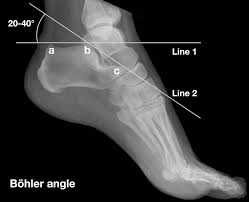

What is Bohler’s angle?